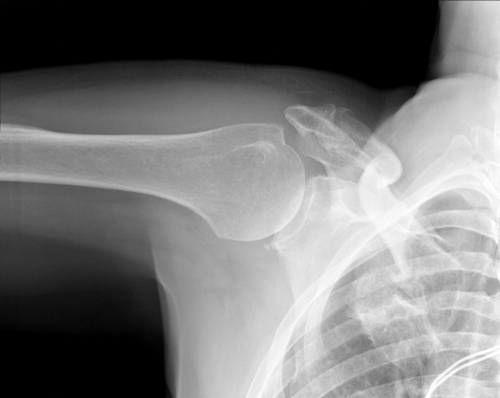

Röntgenbild som visar nyckelbensfraktur. Foto: Shutterstock

Ett brutet nyckelben (nyckelbensfraktur) är ett vanligt benbrott. Det förekommer oftare hos barn och ungdomar, över hälften av frakturerna drabbar barn under tolv år.

Många nyckelbensfrakturer är den typ av brott som kallas för “greenstick”. I dessa fall bryts inte nyckelbenet av; det böjs istället lite grann, ungefär som när man försöker böja en tunn gren på ett träd. Greenstickfrakturer drabbar oftast barn under tolv år.

Behandlingen av ett brutet nyckelben beror på hur frakturen ser ut. I många fall kan en läkare fastställa att det handlar om en nyckelbensfraktur genom att undersöka och ställa frågor. Vissa arm- och axelrörelser leder till smärtor och det är även vanligt att den skadade håller armen nära kroppen för att få mindre ont. Nyckelbensfrakturer hos vuxna brukar röntgas så att skadans omfattning kan bedömas. Hos barn behövs oftast ingen röntgen.